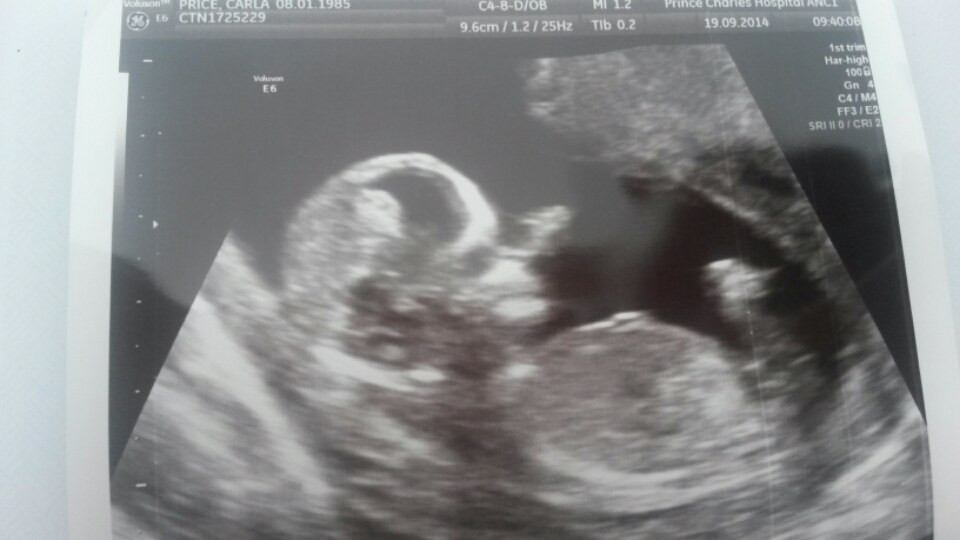

Hi ladies, I am new here and just looking for advice if possible. I had my 20 week scan last week, I was 19+6 and have only now noticed what looks like boy parts on one of the photos. It is a profile shot not potty and it almost looks like a cartoon drawingAttachment 22112! Is this what I'm seeing? It does like quite high up though. Thanks for looking!